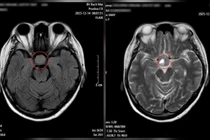

Chị được gia đình đưa đến Bệnh viện Đa khoa Xuyên Á thăm khám, kết quả chụp cộng hưởng từ (MRI) cho thấy có khối u vùng tuyến yên, kèm tình trạng xuất huyết trong u – một biểu hiện của bệnh lý đột quỵ tuyến yên.

Cô gái trẻ không ngờ tình trạng đau đầu lại do đột quỵ tuyến yên - Ảnh BVCC